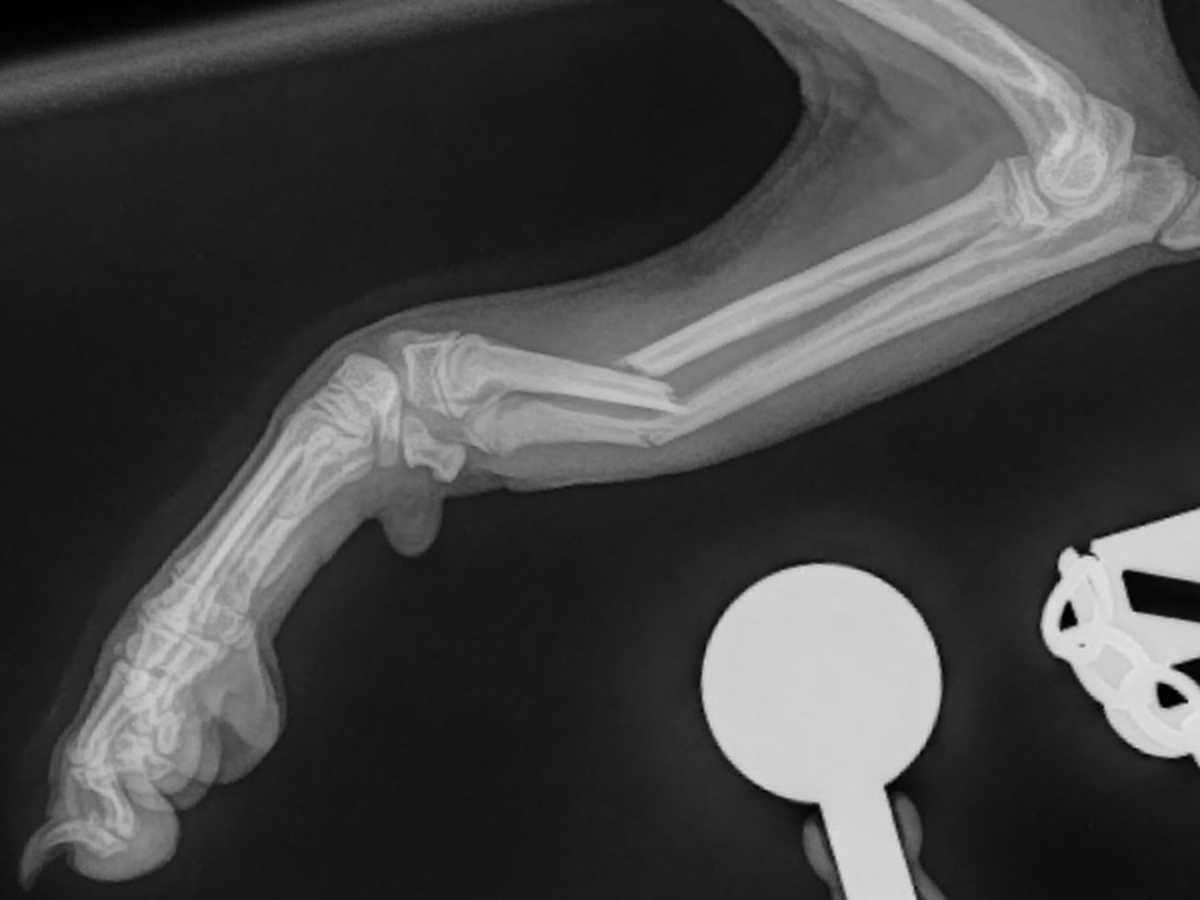

Right now, our hearts are breaking. While playing, Youki broke his leg. It has been temporarily splinted, but the orthopedic vet told us that without surgery his leg may not heal properly. Hearing that was devastating. The operation and costs £5000, and despite our desperate efforts, the insurance company cannot cover it. We are heartbroken because we simply cannot afford this amount, yet we know surgery is his best chance to recover and live the joyful, active life he deserves.

He is only 5 months old. Instead of enjoying walks, socialising with other dogs, and learning through puppy training, he is in pain and missing out on the precious early experiences that shape a happy and confident dog. It’s crushing to watch him confined and hurting, when he should be out exploring the world.